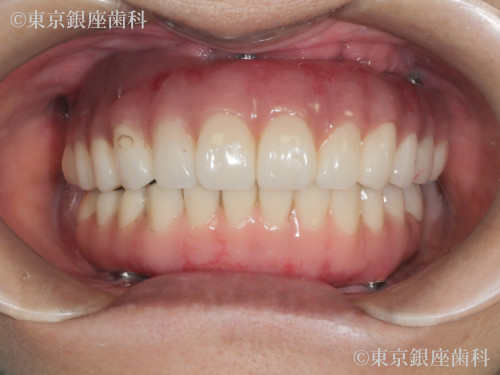

過去のインプラントで十分な結果が得られず再チャレンジし噛む機能を取り戻した60歳代女性の症例

After

以前のインプラントが不十分で再治療を希望。下顎から先にインプラント、上顎洞炎治療後に上顎も実施。難症例ながら最終的に噛める状態を獲得。

上下ワンデイインプラント(再チャレンジ症例)